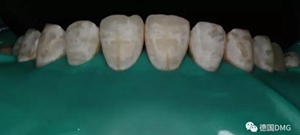

2,使用紅標(biāo)45μm微米和黃標(biāo)25μm粒度車(chē)針仔細(xì)緩慢打磨去除釉質(zhì)表面高氟鈣化的斑塊和釉質(zhì)凹坑0.05-0.1mm后,車(chē)針打磨后要再使用低速慢機(jī)用矽粒子拋光去除釉質(zhì)表面浮釉(松風(fēng)矽粒子、樹(shù)脂拋光輪),下圖是微打磨后。

(下圖是上頜打磨后與下頜術(shù)前未研磨對(duì)比,區(qū)分打磨效果和目的)

治療完成的上頜牙齒和未治療的下頜牙齒形成明顯對(duì)比。